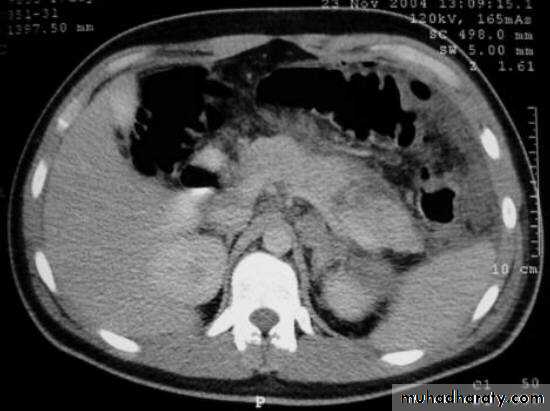

Chronic pancreatitis

Pancreatic carcinoma

Irresectable